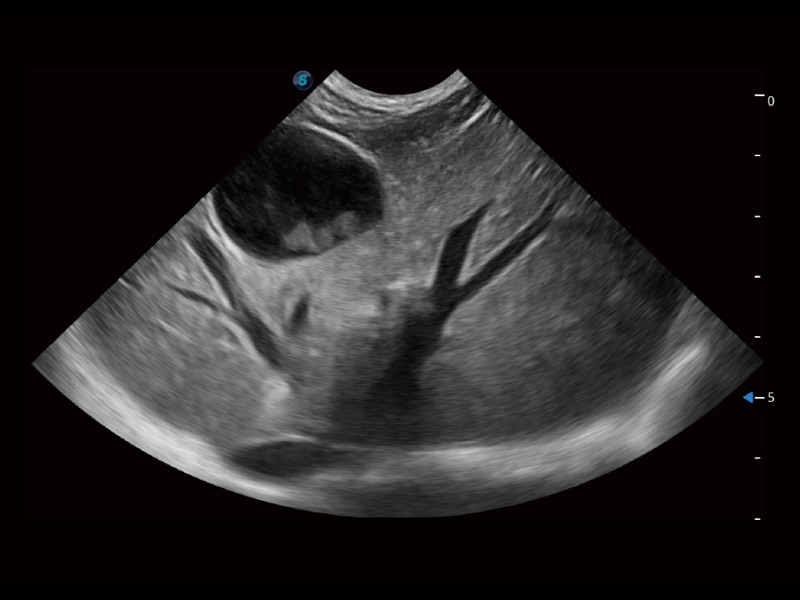

通过创新的 Matrix E自适应滤波器和超长时间域算法,极大提升超低速微细血流的检出能力,同时更精准地滤除软组织和噪声信号,为兽用医生提供以往无法通过常规血流获得的疾病诊断信息。

通过色彩血流和实时宽景相结合,可观察到完整的静脉或动脉的血流,方便医生检查。实时扫查过程中,如有任何操作失误也可以很容易地进行回扫擦除,而不会中断扫查。

一键自动识别膀胱壁及自动测量膀胱容积,不受膀胱形状和大小的限制,帮助医生快速精准获得测量的数据。